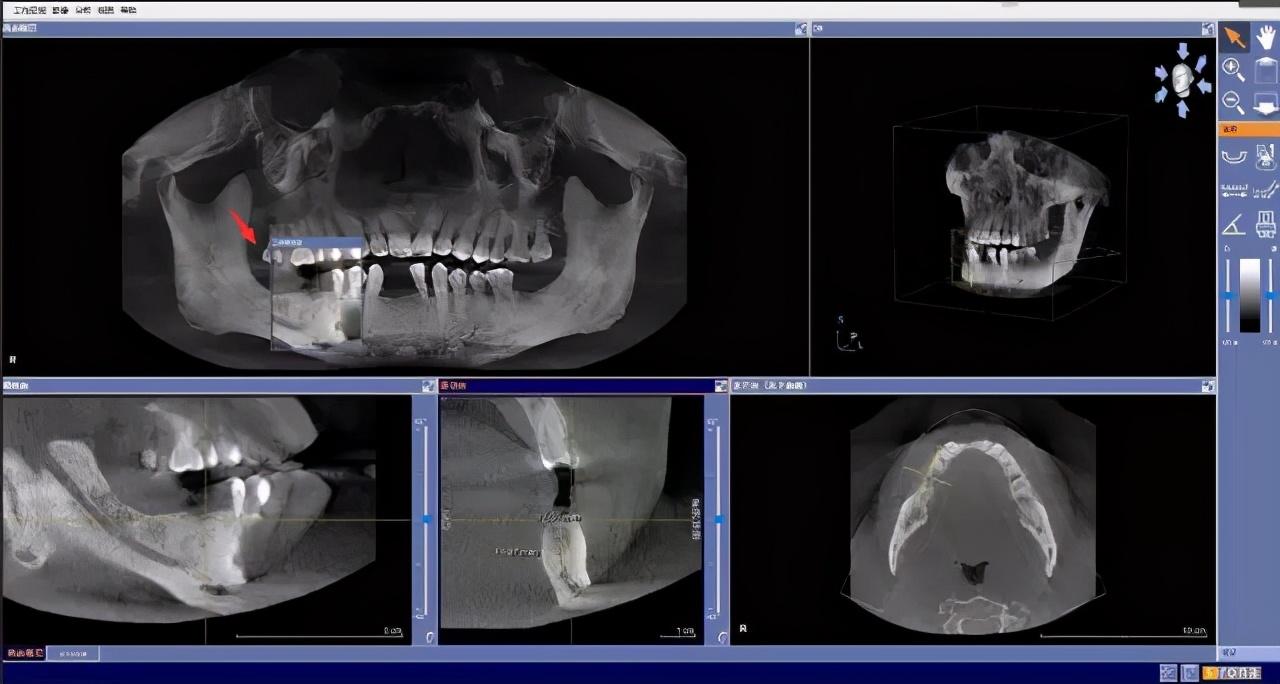

先要做一個(gè)口腔全景片、頜骨CT等

醫(yī)生根據(jù)機(jī)器成像查看口腔的具體情況,

是否有炎癥、牙槽骨的密度、吸收狀況

以及鄰牙組織、牙體組織等。

注明:此數(shù)據(jù)僅作模擬,不是確切種植數(shù)據(jù)。

如果僅靠雙眼大致估測口內(nèi)數(shù)據(jù),是無法得到的高度、寬度的,也無法確認(rèn)骨頭吸收多少,是否需要植入骨粉。

對后期手術(shù)有一定的影響。

通過全景片可以“解剖”牙齒測量,適宜的種植角度也可確定,健康有保障。